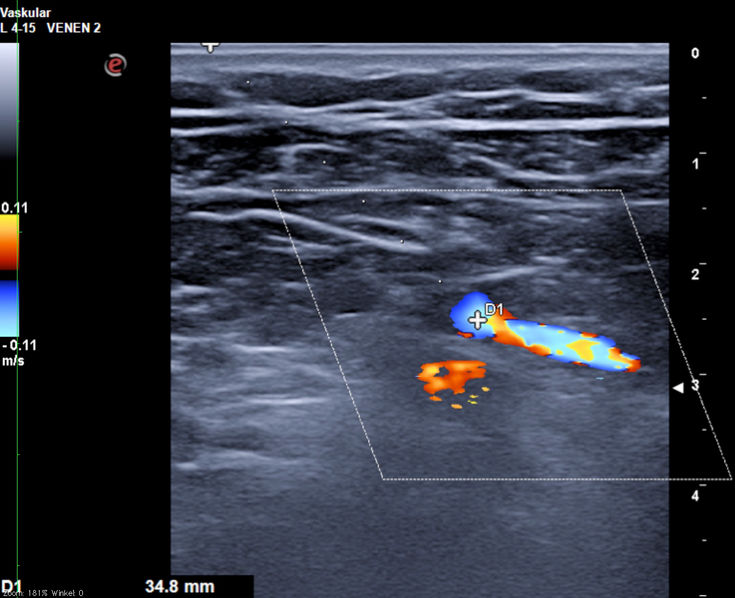

Goldstandard ist die Punktion der rechten Vena jugularis/anonyma supraklavikulär nach oder unter sonographischer Kontrolle. Die Sonographie muß Lagevarietäten klären und Thrombosen nach früherer Katheterisierung ausschließen.

Die Vena jugularis/ Vena anonyma kann nach Yoffa zwischen medialem und lateralem Kopf des Musculus sternocleidomastoideus von ventral punktiert werden oder horizontal von lateral. Diese Methode wurde 1972 von den amerikanischen Herzchirurgen Garcia, Mispireta und Pinho nach ausführlichen anatomischen Präparationen als einfachster und ungefährlichster Zugang beschrieben. Das Zielgebiet, der Zusammenfluß von Vena jugularis und Vena subclavia zur Vena anonyma ist so groß, dass die Punktion auch ohne Sonographie immer beim ersten Stich gelingt.

Die Punktion von ventral kann unter realtime Sonographie mit einem Standardschallkopf wegen des geringen Abstands zur Clavicula nur in der kurzen Schallachse erfolgen, wobei die Nadel nur abschnittsweise sichtbar ist. Mit dem kleinen 22 MHz Fingerschallkopf aus der Rheumatologie ist auch eine Punktion in der langen Schallachse möglich.